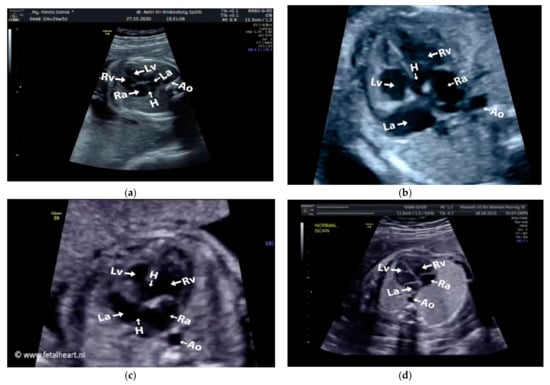

Images with inappropriate anatomical planes (cropped or badly captured) and those with calipers were excluded. The dataset composition was clearly imbalanced (some classes were more frequent than others), as is usually the case in real clinical scenarios. The sample of the raw ultrasound image was based on four views in normal anatomy, as depicted in Figure 2. In such sample, there are the left atrium (LA), left ventricle (LV), right atrium (RA), right ventricle (RV), ductus arteriosus (DUCT), superior vena cava (SVC), aorta ascendens (AoA), aorta descendens (Ao), and main pulmonary artery (MPA), whereas the sample of the raw ultrasound image of abnormal anatomy structure, with the three heart defects such as ASD, VSD, and AVSD condition, is compared to normal anatomy structure in Figure 3. In the abnormal structure, there are hole (H) as heart defect in each condition. Each defect has the variation of hole size; such hole size indicates the disease severity. However, in this study, we only detected the hole, without measuring the hole size.

Figure 2.

Fetal heart scan in four standard views of normal anatomy: (a) 4CH; (b) LVOT; (c) RVOT; and (d) 3VT.